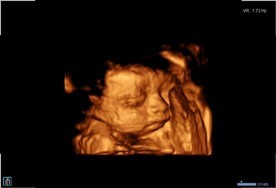

บ้านนี้กำหนดคลอด ก.พ. อยากเห็นลูกแล้วตื่นเต้น ไปซาวด์ 4D มา มีแก้มเยอะคุณหมอแอบแซว ชอบเอามือ เอาแขนบังหน้า 🤣🤣 แม่ๆคนไหนซาวด์แล้วเอาลูกมาอวดกันค่ะ